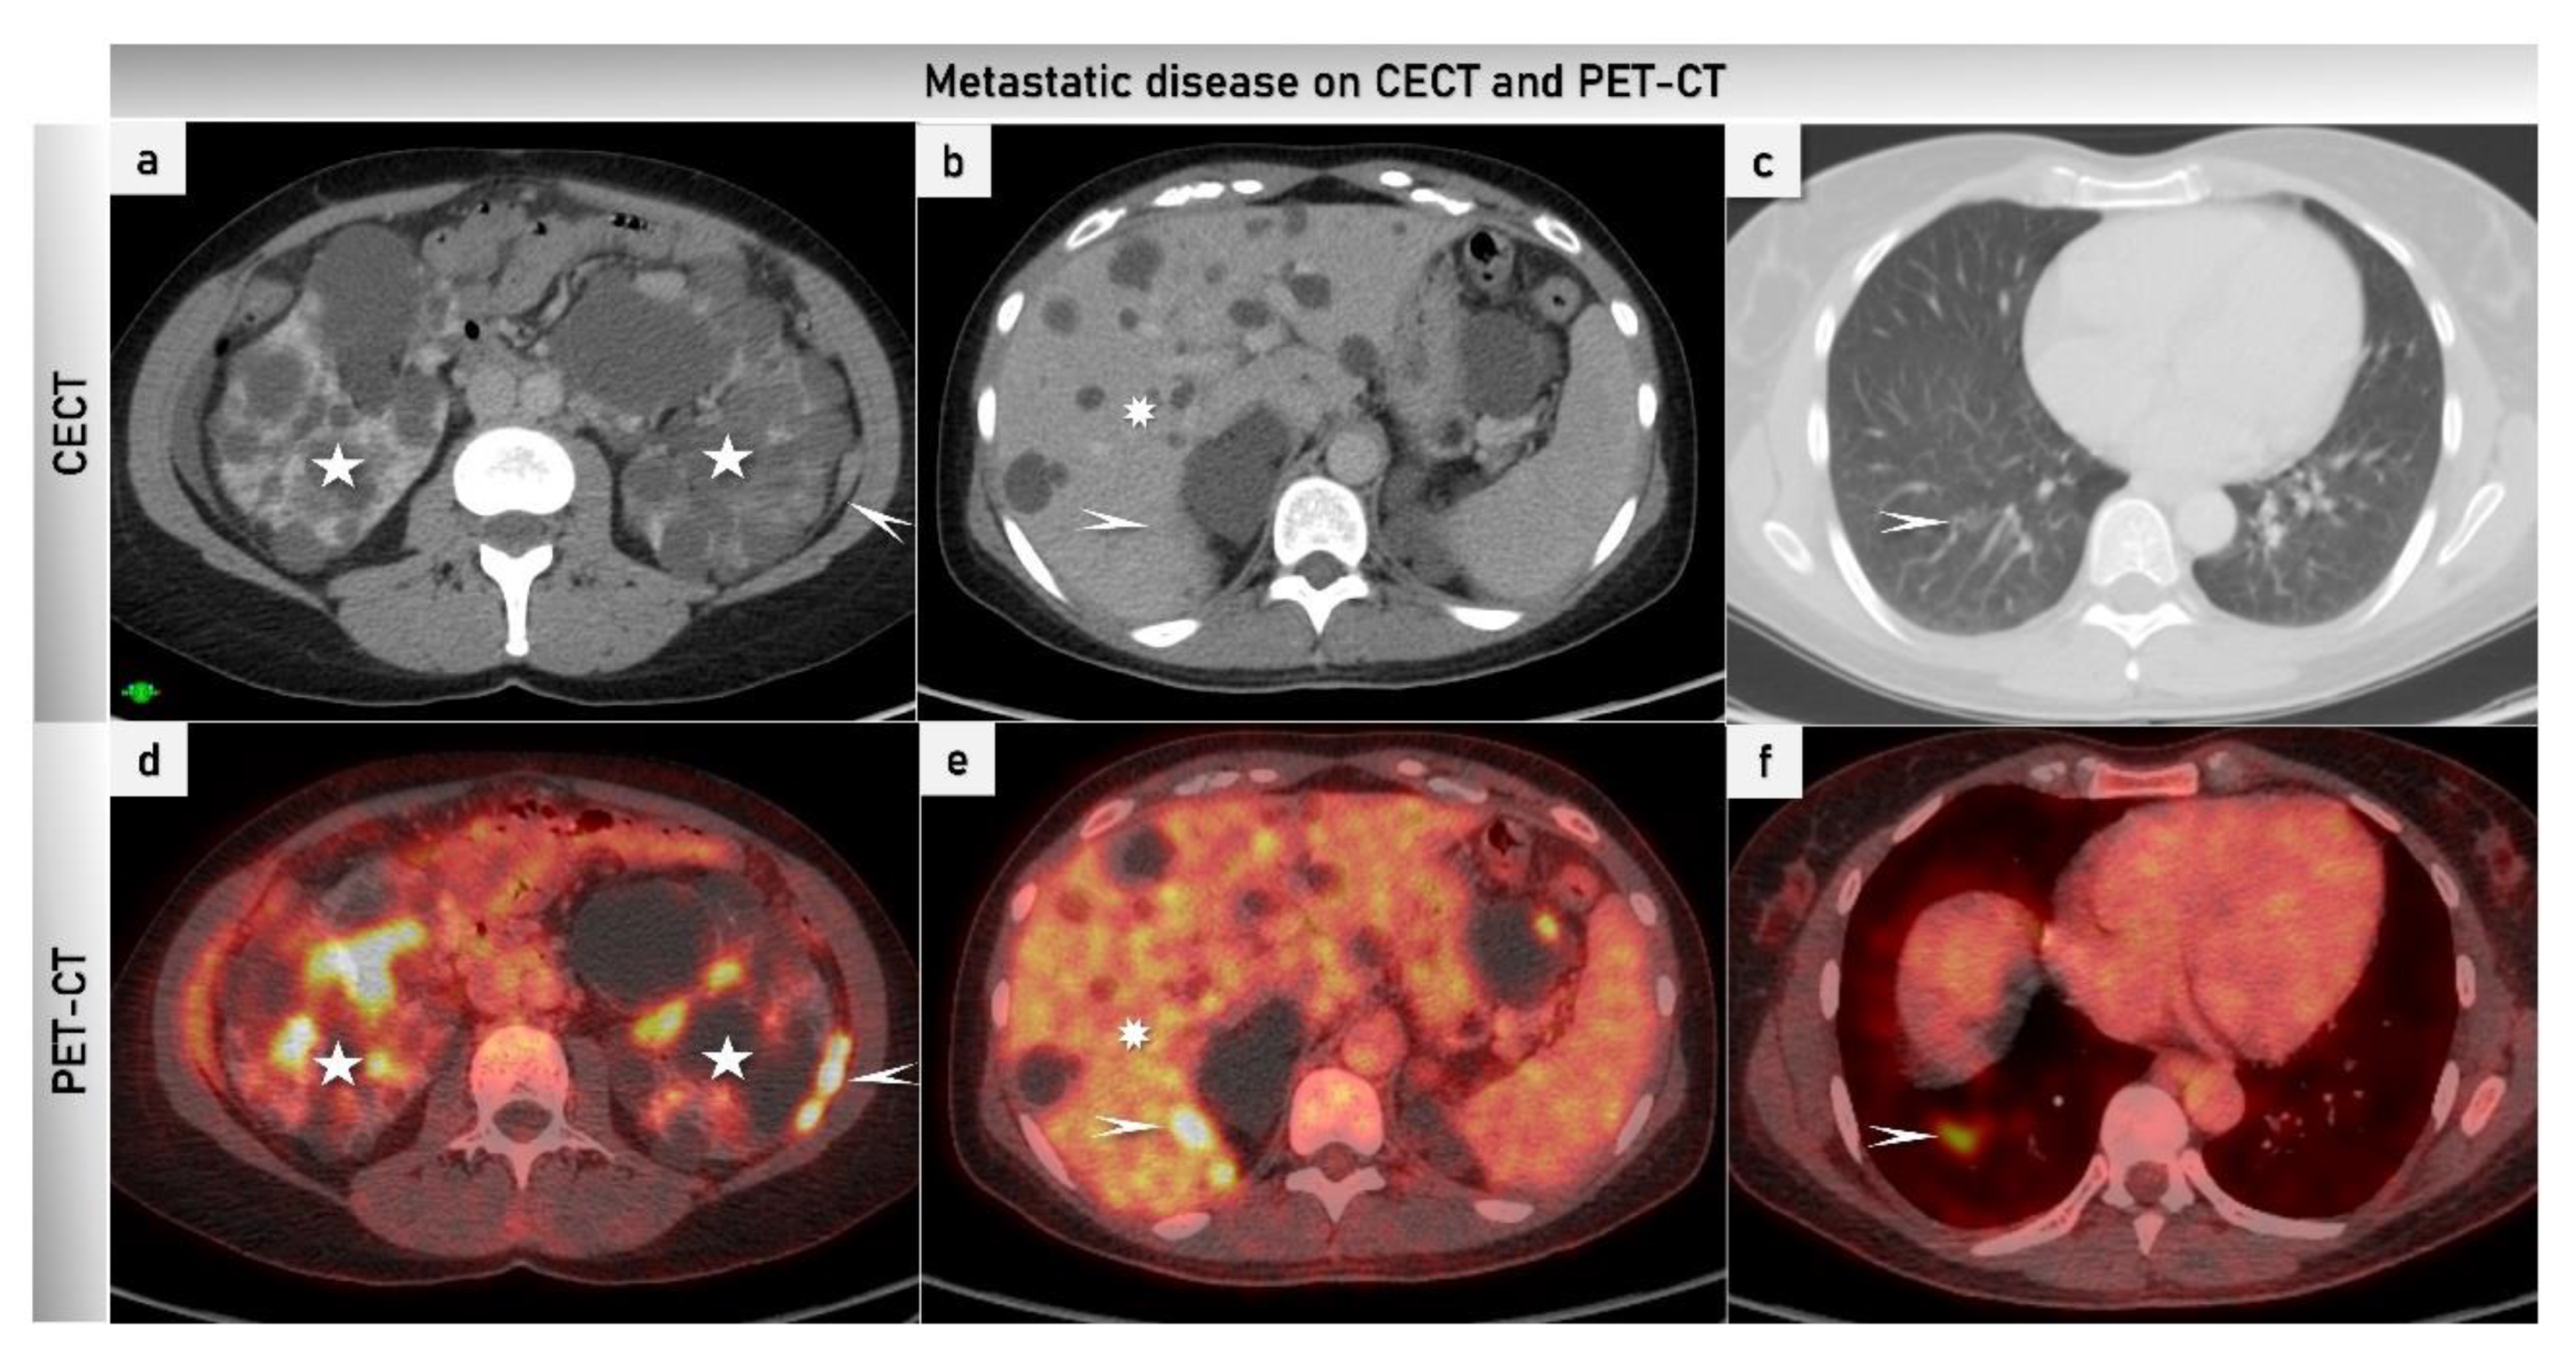

2.3.4. Positron Emission Tomography

3. Future Studies